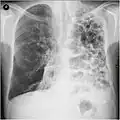

A chest X-ray is not useful to establish a diagnosis of COPD, but it is of use in either excluding other conditions or including comorbidities such as pulmonary fibrosis and bronchiectasis. Characteristic signs of COPD on X-ray include hyperinflation (shown by a flattened diaphragm and an increased retrosternal air space) and lung hyperlucency.[5] A saber-sheath trachea may also be shown that is indicative of COPD.[111]

A CT scan is not routinely used except for the exclusion of bronchiectasis.[5] Pulse oximetry measurement of peripheral oxygen saturation is recommended in people with clinical signs of respiratory failure or right heart failure.[5] An analysis of arterial blood is recommended in those with a peripheral oxygen saturation of 92% or less to determine actual blood oxygen level and assess for high levels of carbon dioxide in the blood, which may have therapeutic implications such as need for non-invasive ventilation or oxygen supplementation.[10] WHO recommends that all those diagnosed with COPD be screened for alpha-1 antitrypsin deficiency.[40]

Lung bulla as seen on chest X-ray in a person with severe COPD

A severe case of bullous emphysema -

Very severe emphysema with lung cancer on the left (CT scan)